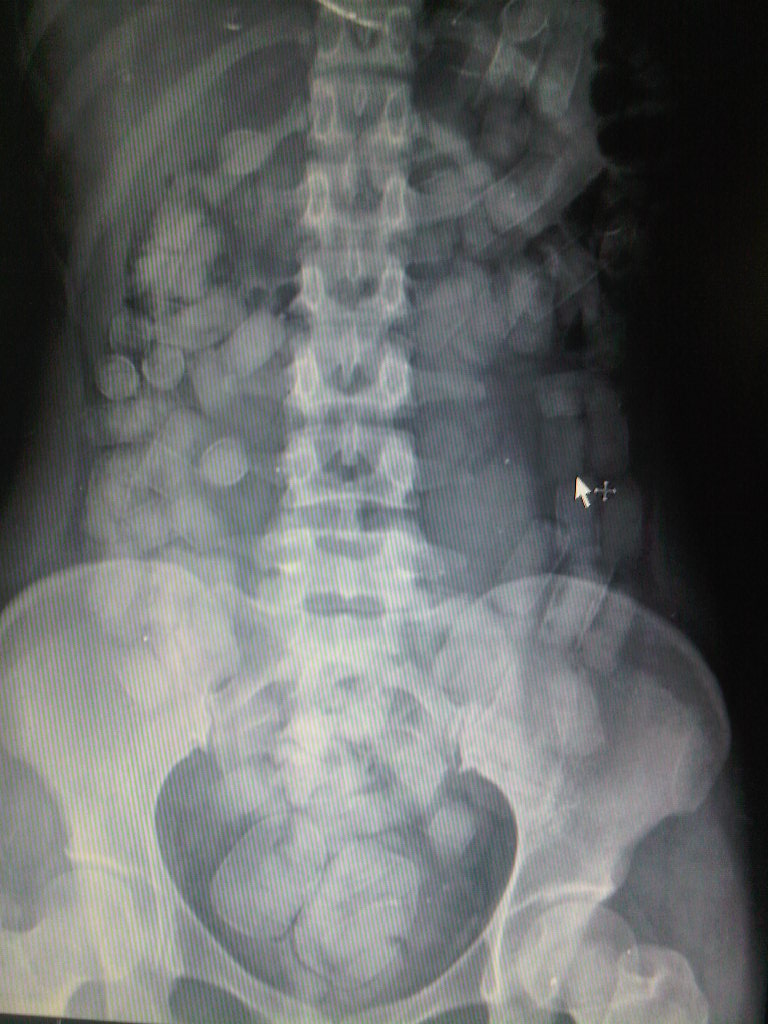

Abdominal Xray of a Body Packer. Multiple tubular foreign bodies are What Is A Body Packer body stuffing is a distinct syndrome from body packing. body packing represents the concealment of illegal substances in a. It occurs when people swallow drug packets to avoid being caught by law enforcement,. The body stuffer is often at risk for acute toxicity. body stuffing is similar to body packing. the “body packer syndrome” arises when. What Is A Body Packer.